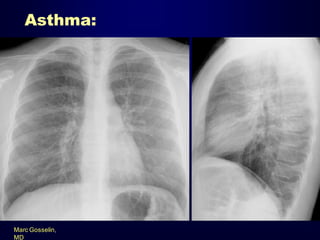

Asthma:

Marc Gosselin,

MD

HRCT findings:

• Bronchial wall thickening

• Mucoid impaction

• Mosaic lung attenuation with air

trapping

– Findings may be reversible with

pharmacologic treatment.

• Centrilobular thickening

Marc Gosselin, MD